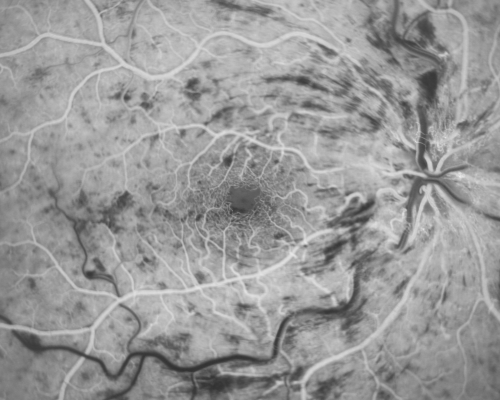

49-year-old woman has central retinal vein occlusion right eye with fluctuating vision for a few month now with OD 20/100. IOP: OD 20

CRVO and CME treated with intravitreal Kenalog 49 Year Old Woman